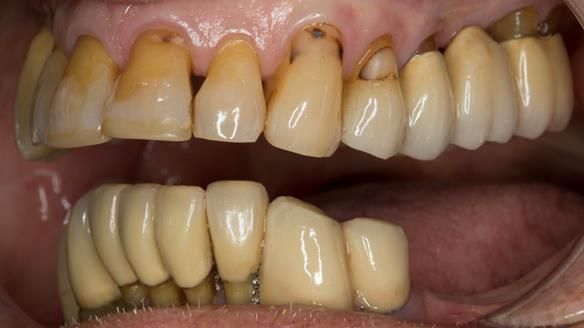

An honest note on the impressions

It’s important to say that I struggled considerably to obtain accurate impressions of Ken’s lower anterior teeth. This was a difficult situation and not one that went smoothly.

At one stage, a tray became locked in position and had to be sectioned and removed carefully. This is not something I like but it does happen, particularly in cases with long, thin teeth and compromised anatomy.

Ken – going downhill, first class

I first met Ken in 2015, when he was 80 years old.

He had lived in both the UK and the USA, spending many years in Florida, where he received extensive dental and periodontal care.

The starting point

We began with the lower jaw.

Final thoughts

This case was always about function, not aesthetics.

Ken’s teeth were never going to look perfect.

There were stained composites, old restorations, and obvious wear.

That was accepted from the outset.

The way Rowan lengthened the teeth — particularly in the upper RPD — to match the existing gingival recession on the remaining teeth was superb. The dentures sit naturally within the context of the rest of the mouth.